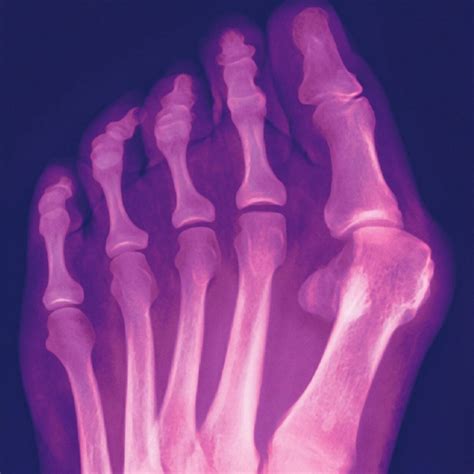

If you have been experiencing persistent pain, swelling, or a visible bump at the base of your big toe, you may be dealing with a hallux valgus, commonly known as a bunion. While physical exams can suggest the presence of this deformity, a Bunion X Ray is the gold standard for clinical diagnosis. This imaging procedure provides orthopedic specialists with a clear look at the internal structure of your foot, helping them determine the severity of the misalignment and the best course of action for long-term relief.

A bunion is not just a simple bump; it is a complex deformity that involves the shifting of bones within the foot. When a doctor orders a Bunion X Ray, they are not just looking for the bump; they are assessing how the metatarsal bone and the phalanges interact. Without an X-ray, it is nearly impossible to tell how much the bones have drifted or whether the joint has begun to show signs of arthritic degeneration.

• Measuring the Angle: Doctors measure the Hallux Valgus Angle (HVA) and the Intermetatarsal Angle (IMA) to quantify the severity of the bunion.

• Joint Health: Identifying cartilage loss or the presence of bone spurs within the joint space.

• Surgical Planning: If surgery is required, the X-ray acts as a blueprint to determine which type of osteotomy or fusion is necessary.

• Identifying Associated Deformities: Often, bunions coexist with hammertoes or flat feet, which can be identified on the same film.

A clinical look at a Bunion X Ray showing bone misalignment